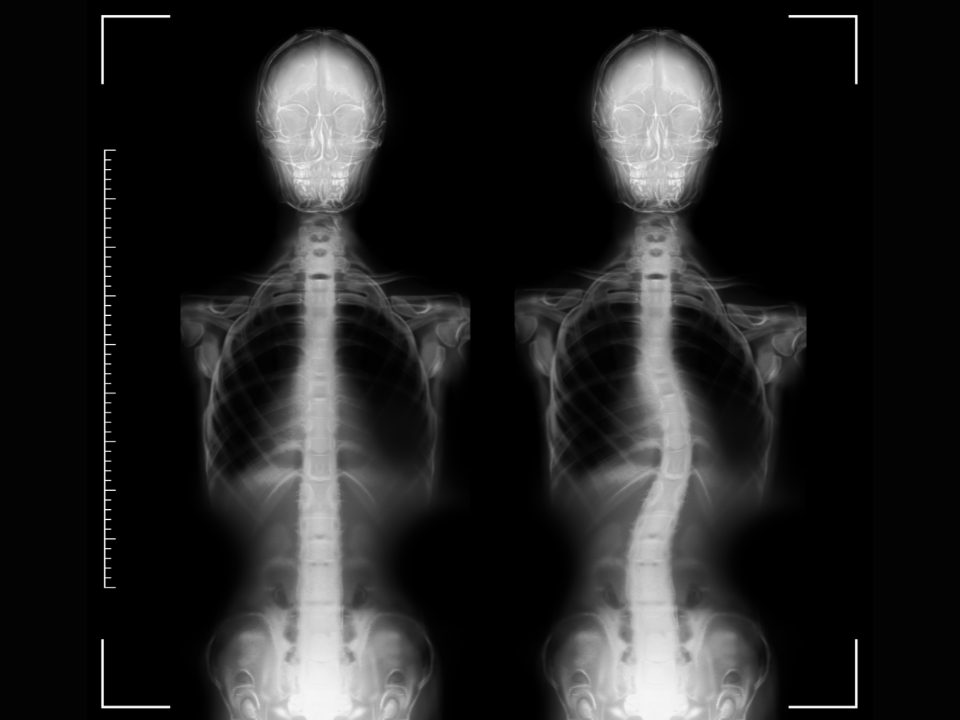

Avanços tecnológicos tornam as cirurgias de coluna mais seguras, precisas e com recuperação mais rápida

Para a maioria das pessoas, receber a notícia de que irá precisar de uma cirurgia da coluna ainda soa como uma sentença, e por muitos anos de fato esses procedimentos estiveram associados a resultados ruins e complicações. Nas últimas décadas, no entanto, a neurocirurgia de coluna tem avançado rapidamente, incorporando técnicas minimamente invasivas e dispositivos inteligentes que transformam a maneira de tratar diversas condições que afetam a coluna vertebral.

Apesar de todos os avanços, é importante salientar que, como em qualquer procedimento cirúrgico, a seleção dos pacientes e o criterioso planejamento pré-operatório são fundamentais para o sucesso do tratamento. A decisão de utilizar uma técnica minimamente invasiva ou um implante inteligente deve ser baseada em uma avaliação detalhada do quadro clínico e das condições anatômicas do paciente. Sempre existirão casos em que a cirurgia convencional ainda será a melhor opção, mas ainda assim, a combinação de diversas técnicas permite que mesmo para esses casos a segurança seja aumentada.